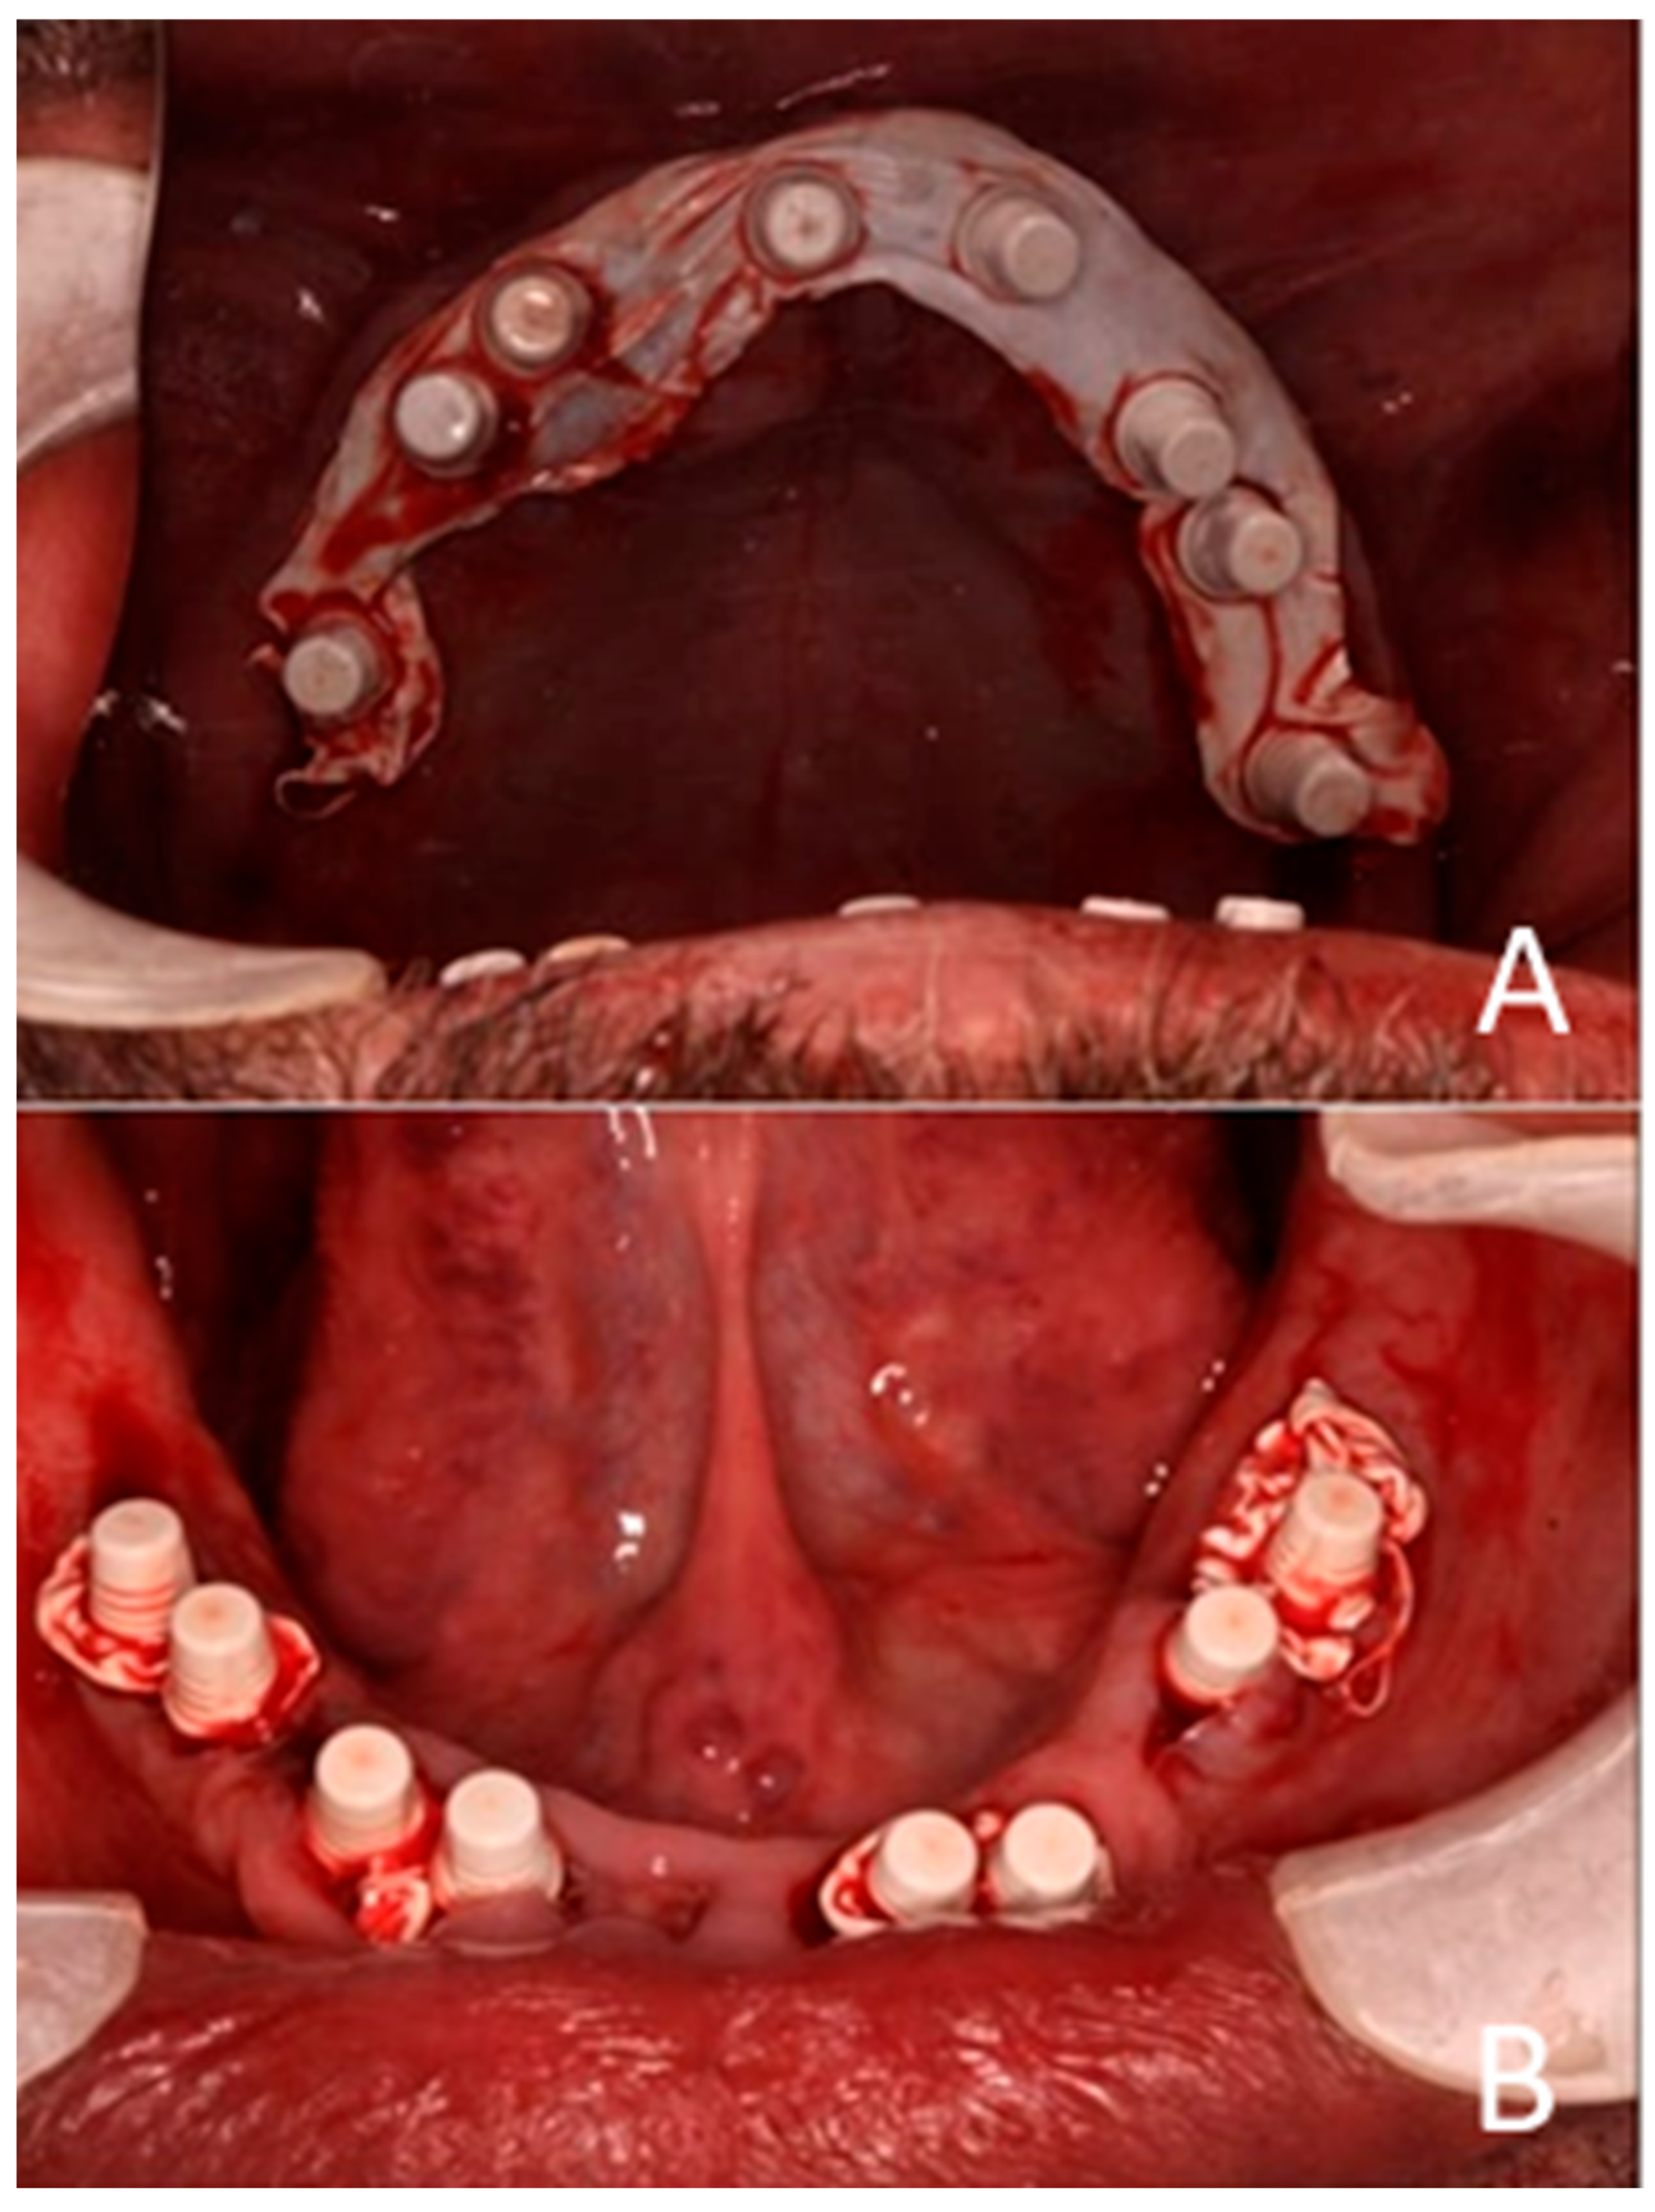

Figure 6. One-piece zirconia implants and abutments are shown. (A) Maxilla. (B) Mandible.

Following implant placement, the incision wounds were left to heal by secondary intention, which resulted in augmentation of the buccal soft tissue (Figure 6).

Each telescopic crown was sandblasted on the internal surfaces, then placed in an ultrasonic bath and treated with the manufacturer-specified “Bredent” solution. A resin cement was utilized to bond each telescopic crown to its respective zirconia abutment. The arches were scanned once again and sent to the lab for the fabrication of segmented zirconia bridges, which were subsequently provisionalized with PEEK crowns (Figure 11, Figure 12 and Figure 13).